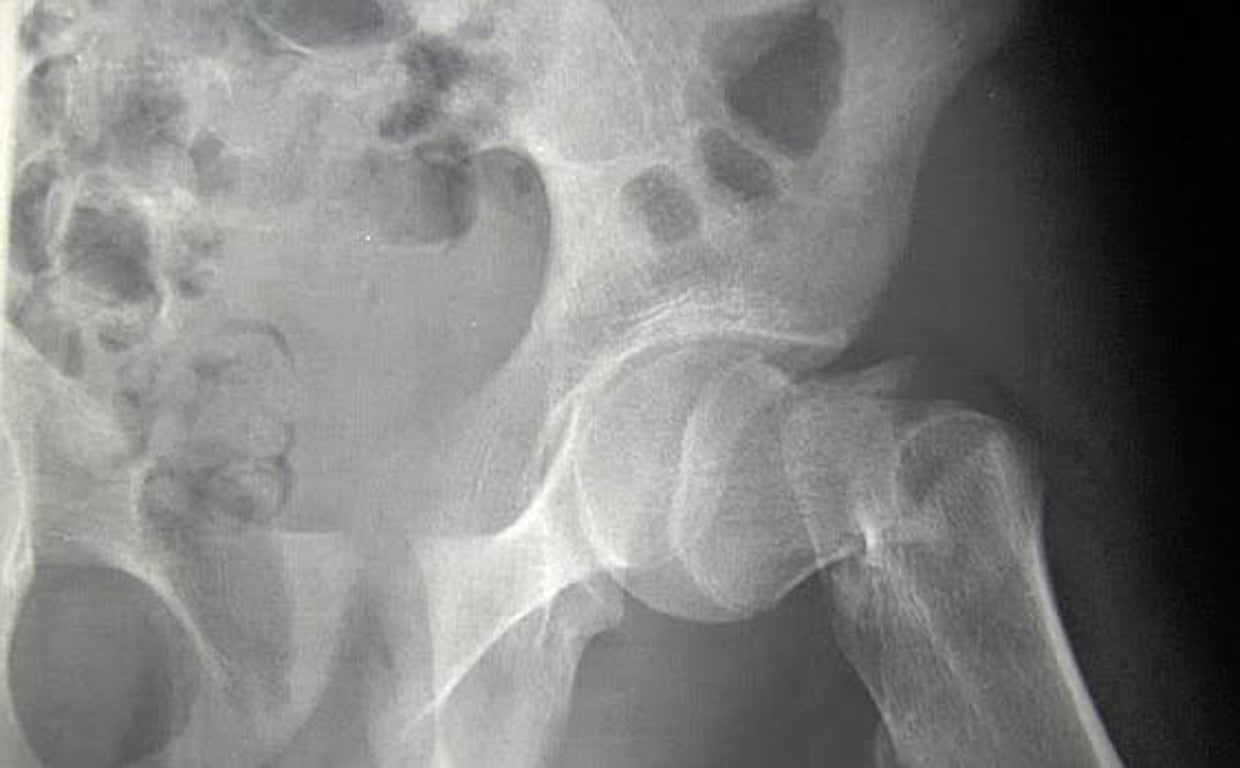

Se confirmaron un total de 1.991 fracturas incidentes en 1.551 participantes durante una mediana de seguimiento de 5,3 años. En comparación con el placebo, la vitamina D3 suplementaria (2000 UI/día) no redujo las fracturas totales, no vertebrales o de cadera. Los análisis también mostraron que no hubo efectos de la vitamina D3 suplementaria en las principales fracturas osteoporóticas, fracturas de muñeca o fracturas pélvicas. Los efectos no se modificaron por la edad inicial, el sexo, la raza, el índice de masa corporal, los niveles sanguíneos iniciales de vitamina D o el uso personal de suplementos de calcio y/o vitamina D.